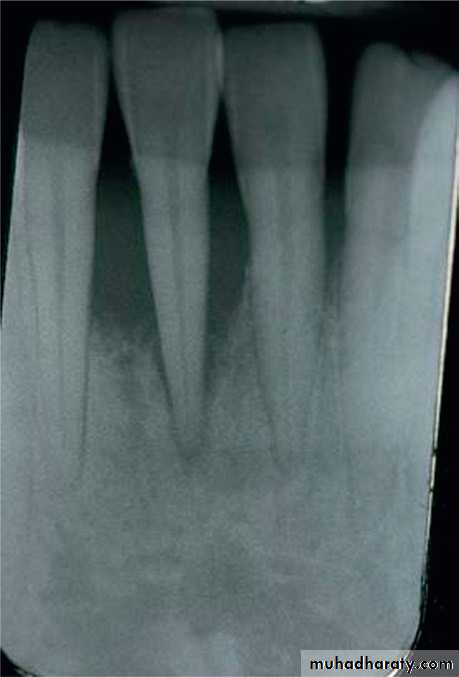

Preoperative radiograph of anterior mandible in localized aggressive periodontitis patient.